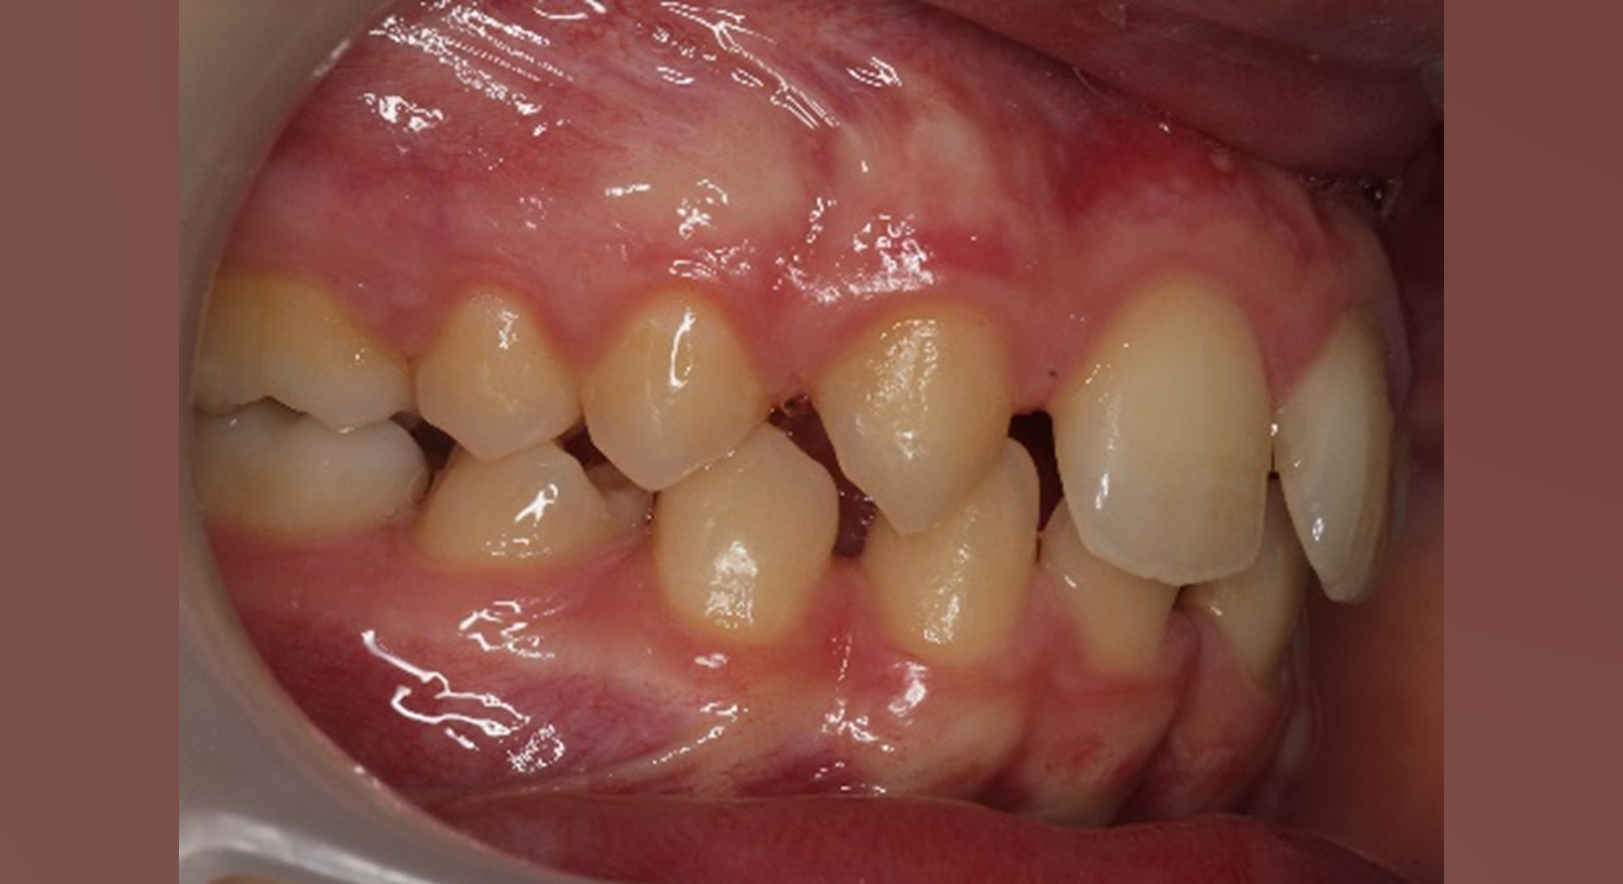

Skeletal Class II due to mandibular retrognathia, proclination of maxillary incisors, narrow arch creating a V-shaped arch, agenesis of 12, 31, 41, hyperdivergent facial pattern, moderate deep bite (2 mm), increased overjet (9 mm), asymmetric canine and molar Class II due to mandibular deviation to the left, maxillary midline deviation related to agenesis of 12, distal rotation of 35 and 45, and pronounced lower curve of Spee.

Labial incompetence, mouth breathing, tongue dysfunction